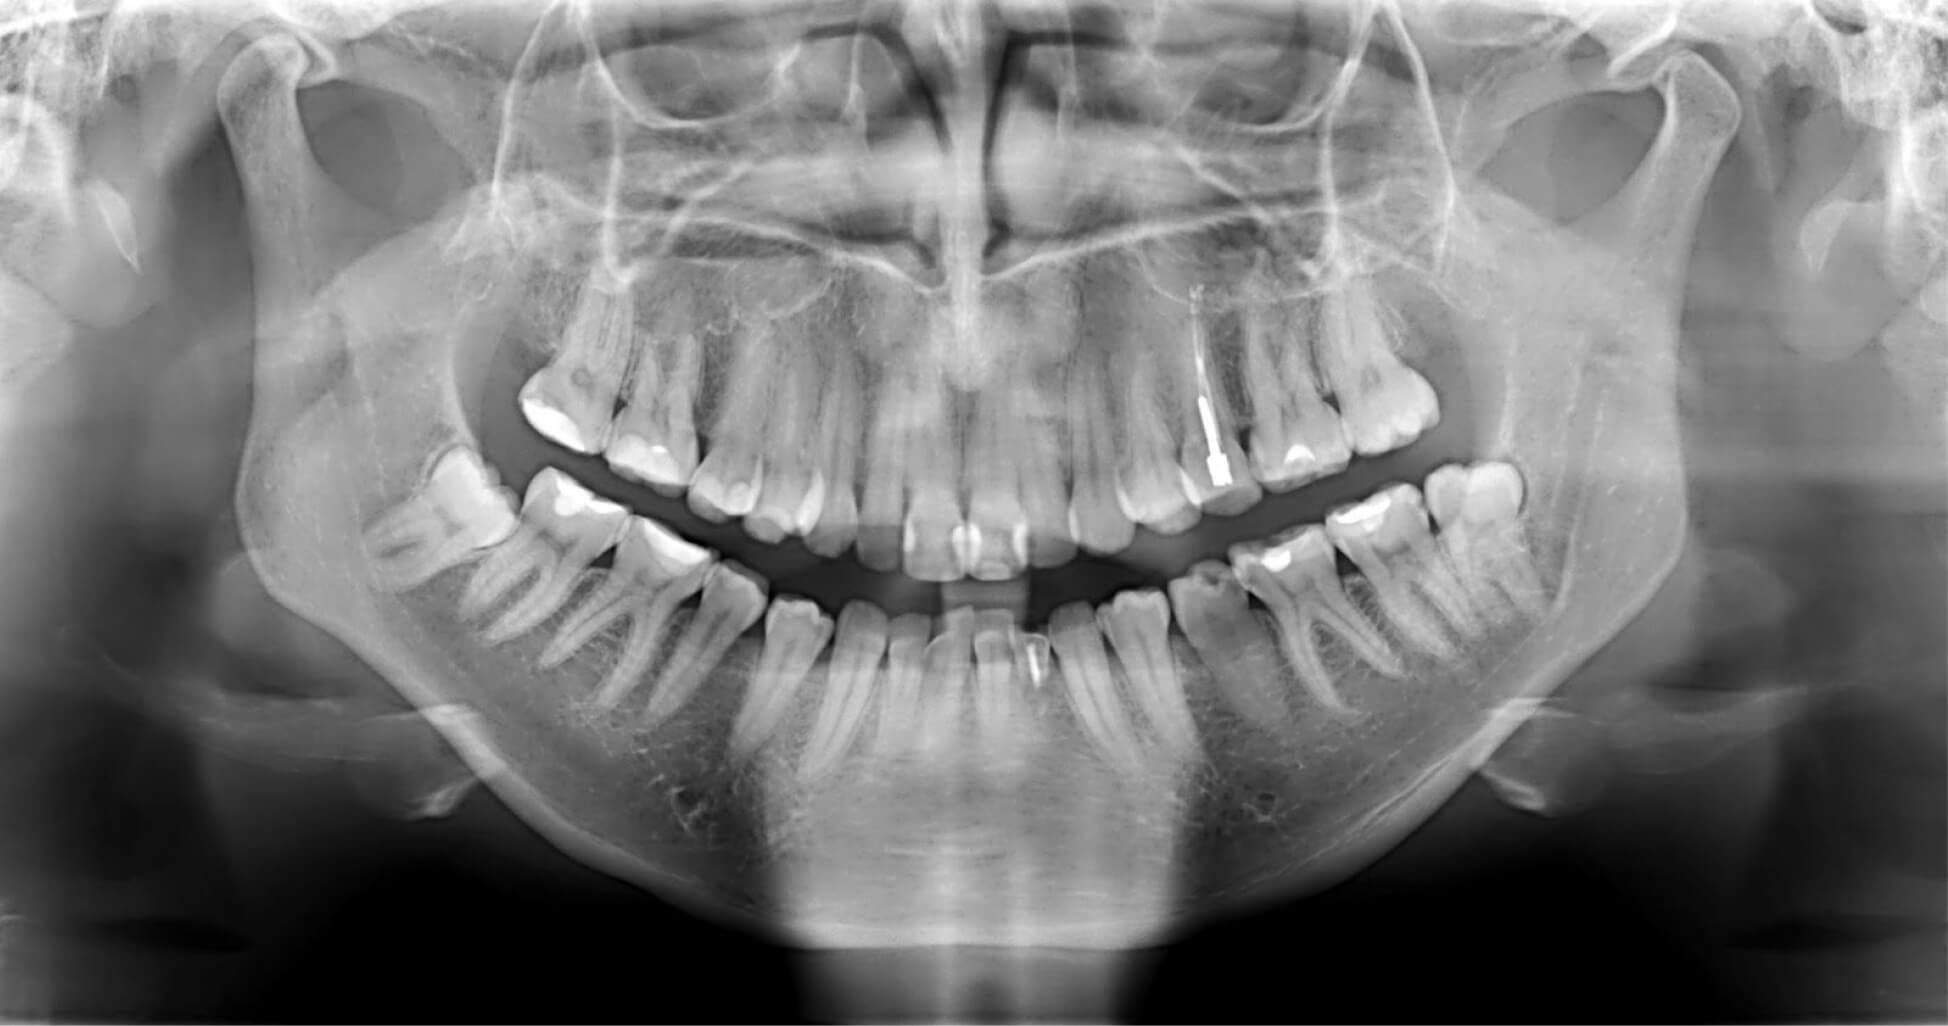

Дентальные снимки и диагностика кариеса